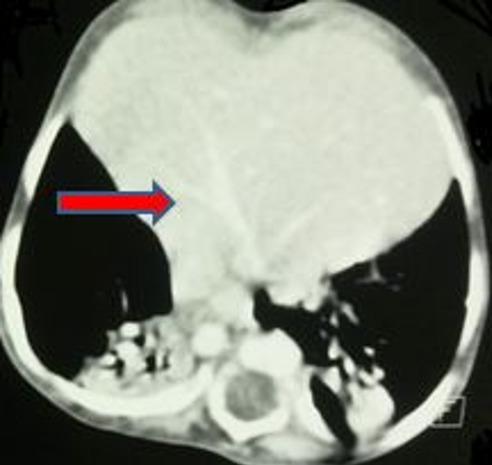

Retro-costo-xyphoidian hernia is a rare congenital malformation. It accounts for 3% of all the diaphragmatic hernias. It can be isolated or associated with other malformations. We here report a very rare case of Morgagni-Larrey hernia and situs inversus totalis detected after neonatal respiratory distress.